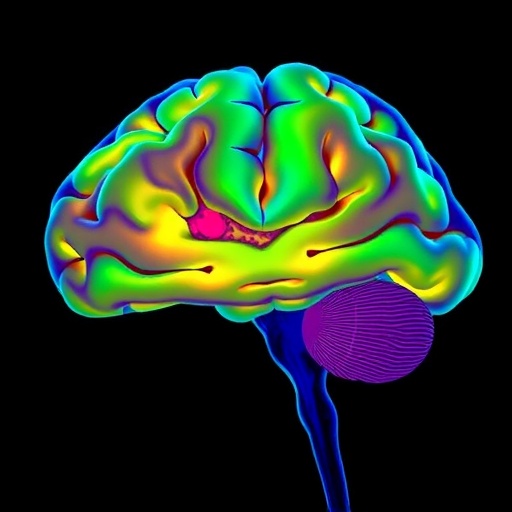

The hippocampus, a pivotal brain structure responsible for memory formation and navigation, has long been understood as a hub for spatial memory consolidation through patterns of neural reactivation during sleep. Yet, the complex interplay between the brain’s spatial and emotional memory systems has remained enigmatic, particularly given the anatomical and functional divisions along the hippocampus’s dorsoventral axis. While the dorsal hippocampus (dHPC) predominantly processes spatial information, it is largely disconnected from key emotional centers such as the amygdala. In contrast, the ventral hippocampus (vHPC) is intimately linked to emotion-related circuits. How these two hippocampal subdivisions synchronize during sleep to unify spatial and emotional aspects of episodic memory has eluded neuroscientists—until now.

In a groundbreaking study published in Nature Neuroscience, Morici et al. (2026) meticulously unravel the cooperative dynamics between the dorsal and ventral hippocampus during sleep, providing crucial insights into how emotional experiences are integrated with spatial memory. By deploying simultaneous electrophysiological recordings in rats engaged in a spatial alternation task framed by either aversive or rewarding emotional contexts, the researchers delivered compelling evidence that coordinated sharp-wave ripples (SWRs) during non-rapid-eye-movement (NREM) sleep orchestrate neural assembly reactivation propagating along the dorsoventral hippocampal axis.

Sharp-wave ripples—high-frequency oscillatory events thought to underlie memory consolidation through neural replay—are traditionally associated with the dorsal hippocampus’s role in spatial reactivation. However, Morici et al. reveal a nuanced mechanism whereby SWRs are not isolated events confined to spatial coding circuits but are network-wide phenomena that engage ventral hippocampal assemblies responsive to emotional stimuli. This joint reactivation suggests a sophisticated form of memory processing during sleep that melds contextual information with the affective valence of experiences.

A distinctive finding from the study highlights that following an aversive task, the reactivation patterns during sleep more faithfully reproduce the original neural ensemble firing observed during wakefulness, particularly within the ventral hippocampus. This fidelity is driven by increased recruitment of vHPC neurons responsive to the shock, alongside enhanced spatial replay activity in the dorsal hippocampus, strengthening the argument that emotional experiences amplify the reconstruction of episodic memories during sleep. Such modulation was less pronounced following rewarding tasks, illustrating how negative emotional valence might uniquely influence the consolidation process.

The technical approach employed by the authors deserves attention: by simultaneously recording from both dorsal and ventral sites, the study overcomes the common limitation of examining hippocampal subregions in isolation. This method allowed the researchers to characterize cross-regional interactions and temporal coordination during SWRs with high precision. Using analyses of neural ensemble spiking patterns and their sequence fidelity, the research illuminated how emotional and spatial information converge within the hippocampus rather than being processed in parallel but segregated pathways.

Moreover, the study’s insights add nuance to the classical model of hippocampal function that compartmentalizes spatial and emotional processing. The demonstration of coordinated SWR-associated reactivation challenges the dichotomy between dorsal and ventral subregions and highlights a dynamic and integrative process where episodic memories are enriched through the convergence of multiple neural representations. This reframing prompts a reevaluation of memory consolidation theories and encourages the exploration of hippocampal subfield interactions in other cognitive domains.

From a broader perspective, this research underscores the critical role of sleep as an active neurophysiological state during which the brain orchestrates the stabilization and integration of complex memories. The coordinated dorsal-ventral replay suggests that sleep-dependent consolidation is not merely a process of reactivation but involves precise temporal coordination across anatomically distinct hippocampal segments. Such synchronization might serve to route integrated information effectively to neocortical and limbic targets, enhancing the emotional salience and contextual richness of episodic memory traces.

In sum, Morici and colleagues provide a compelling advance in our understanding of how the brain synthesizes the spatial and emotional dimensions of experience during sleep. Their demonstration that coordinated dorsoventral hippocampal reactivation during SWRs represents a neural substrate by which episodic memories are enriched with affective meaning will undoubtedly influence theoretical models of memory and guide experimental approaches across neuroscience disciplines. This work elegantly illustrates the brain’s remarkable capacity for integrating multifaceted information even as the organism rests, a testament to the complexity of memory consolidation processes underpinning cognitive and emotional functioning.

Ultimately, the finding that the hippocampus functions as an integrated dorsoventral network during sleep—melding spatial maps with emotional context—reframes a classic brain region as a nexus of memory richness. Sleep is not merely downtime but a stage where the brain weaves together the fabric of lived experience, emotion, and place into the durable tapestry we call episodic memory.